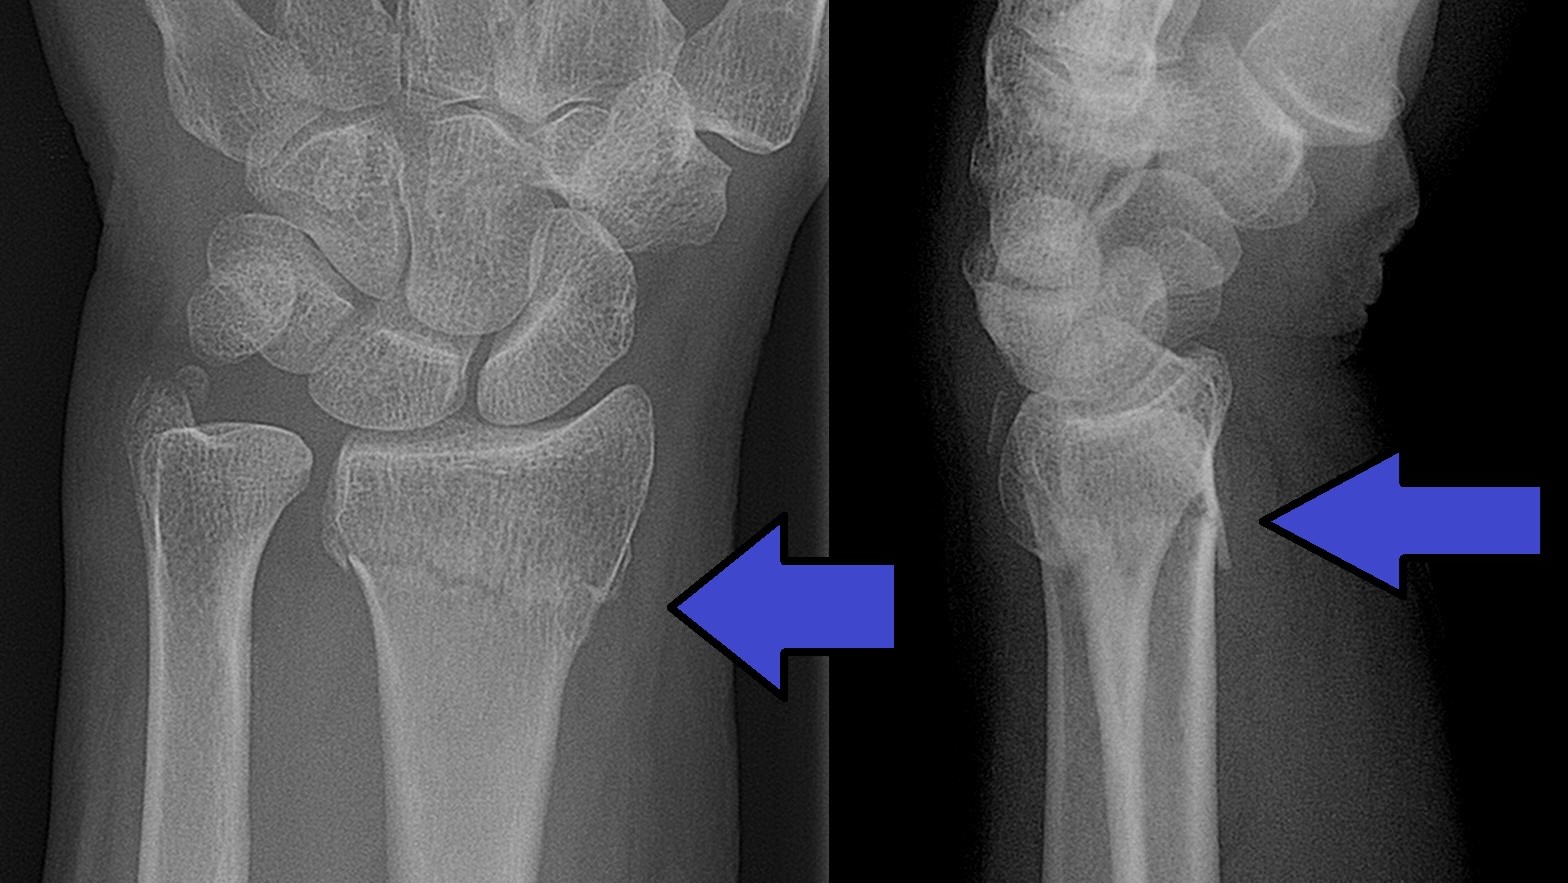

Distal radiusfraktur (handled)

Distal radiusfraktur är den vanligaste frakturen överhuvudtaget. Drabbar oftast kvinnor med osteoporotiskt skelett (fallskada inomhus eller utomhus vid halka). Högenergiskador i samband med trafikolyckor och sport drabbar vanligen yngre individer.

Olika distala radiusfrakturer

- Dorsal felställning: Colles fraktur

- Volar felställning: Smiths fraktur

- Volar felställning med intraartikulärt engagemang: Smith-Barton fraktur

Behandlingen bör individualiseras och bygga på klassificering av frakturen i olika svårighetsgrader.

Smith fraktur och Smith-Barton fraktur är ofta instabila och kräver rigid fixation, Smith-Barton oftast med volart anbringad frakturplatta. Colles fraktur kan ibland behandlas enklare, exempelvis med dorsal gipsskena. Denna fraktur dislocerar dorsalt, men även med axial kompression av radius. Graden av radiusförkortning anses påverka slutresultatet och kraftig förkortning bör därför reponeras.

Behandlingen kan utgå från ett klassificeringssystem, exempelvis Older som delar in frakturer i 4 typer beroende på initial felställning.

- Typ 1: liten felställning, radiusförkortning < 2 mm

- Typ 2: mer uttalad felställning, radiusförkortning 2-5 mm

- Typ 3: uttalad felställning med komminut fraktur av dorsala cortex, radiusförkortning > 5mm

- Typ 4: intraartikulär komminut fraktur med kraftig felställning.

Operationsindikation föreligger (om vital patient)

- Ulna+ 2-3 mm

- Dorsalbockning > 20° (mätt från normal/ursprungsläget)

- Hak i ledytan > 1-2 mm

Operation sker med volar platta.